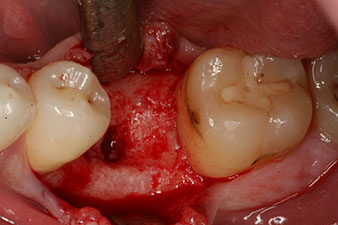

Figura 1: Situación clínica inicial después de la cicatrización del alvéolo de extracción de la pieza 36: la base del hueso es ancha y existe una cantidad suficiente de encía queratinizada.

En el paciente de 28 años con un historial de fumador severo, fue preciso extraer la pieza dental 36 como consecuencia de una recidiva de una periodontitis apical.

Como las piezas dentales adyacentes estaban en su mayoría intactas, el único tratamiento posible para los huecos existentes era un implante.

Figura 2: Seis semanas después, se observó un alvéolo que solo estaba osificado de forma incompleta en el área de la raíz mesial.

No obstante, seis semanas después de la extracción, tras la disección del colgajo mucoperióstico, se observó una osificación incompleta en el área del antiguo alvéolo mesial.